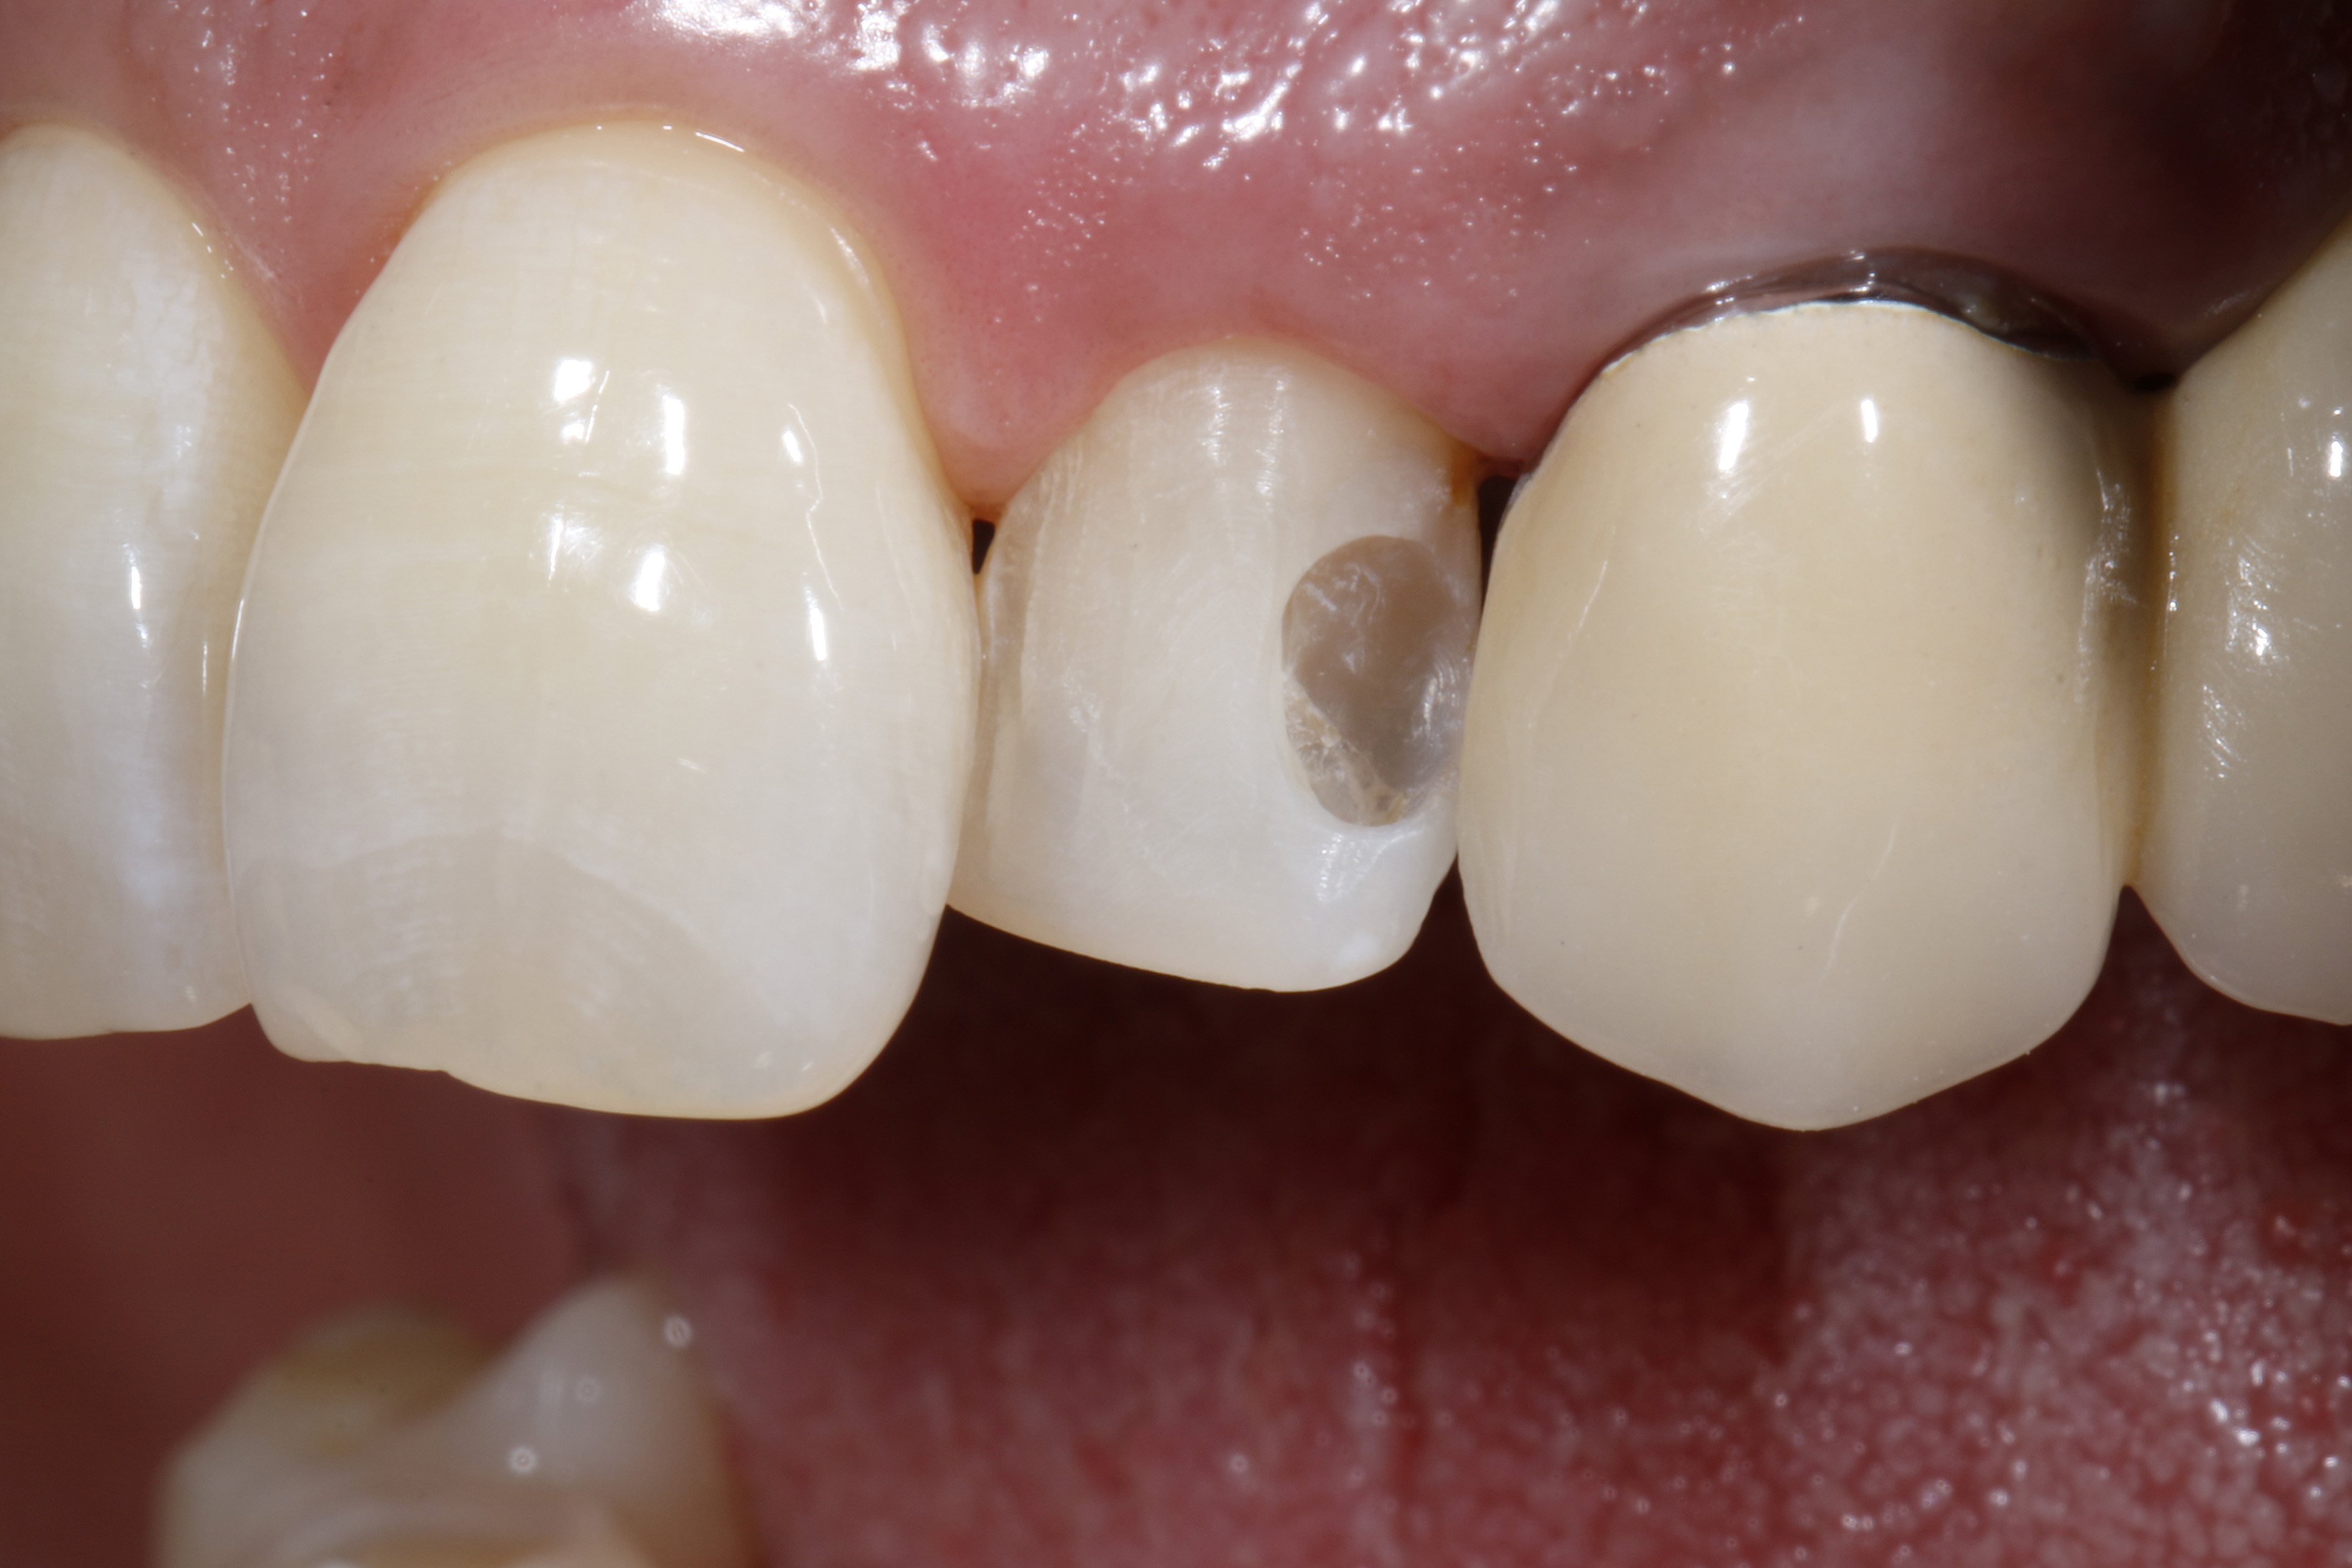

Do naszego gabinetu stomatologicznego zgłosiła się 60-letnia pacjentka z prośbą o lepsze optyczne ustawienie w łuku zębowym lewego bocznego siekacza szczęki, który jest wyraźnie położony podniebiennie w stosunku do lewego siekacza centralnego (ryc. 1 i 2).

Oprócz samego zęba, pacjentce szczególnie przeszkadzał fakt, że ząb wydawał się znacznie ciemniejszy w uśmiechu w porównaniu z lewym siekaczem centralnym i koroną PFM na lewym kle. Ząb bezzwłocznie zareagował nadwrażliwością na test na zimno, nie wykazał przy tym nieprawidłowości w teście opukiwania. Po zapoznaniu się z możliwymi alternatywami leczenia i ich kosztami, pacjentka zdecydowała się na licówkę bezpośrednią z użyciem uniwersalnego kompozytu GrandioSO Unlimited (VOCO GmbH, Cuxhaven).

Ryc. 1, 2. Sytuacja wyjściowa: lewy siekacz boczny jest ustawiony wyraźnie podniebiennie w stosunku do zębów sąsiednich. To przeszkadza pacjentce, który chciałaby uzyskać lepszą integrację wizualną z łukiem zębowym.